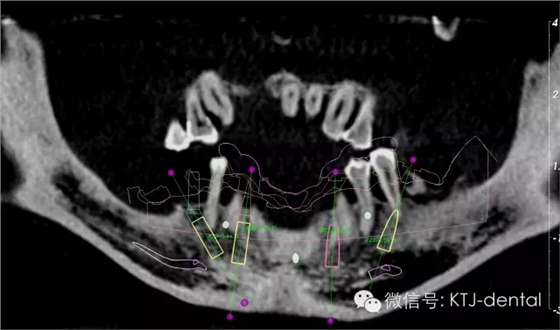

640.webp (3).jpg

圖3-4 三維立體顯示設(shè)計(jì)圖